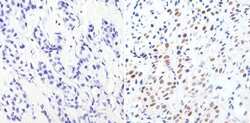

Immunohistochemistry

MA1-028 IHC